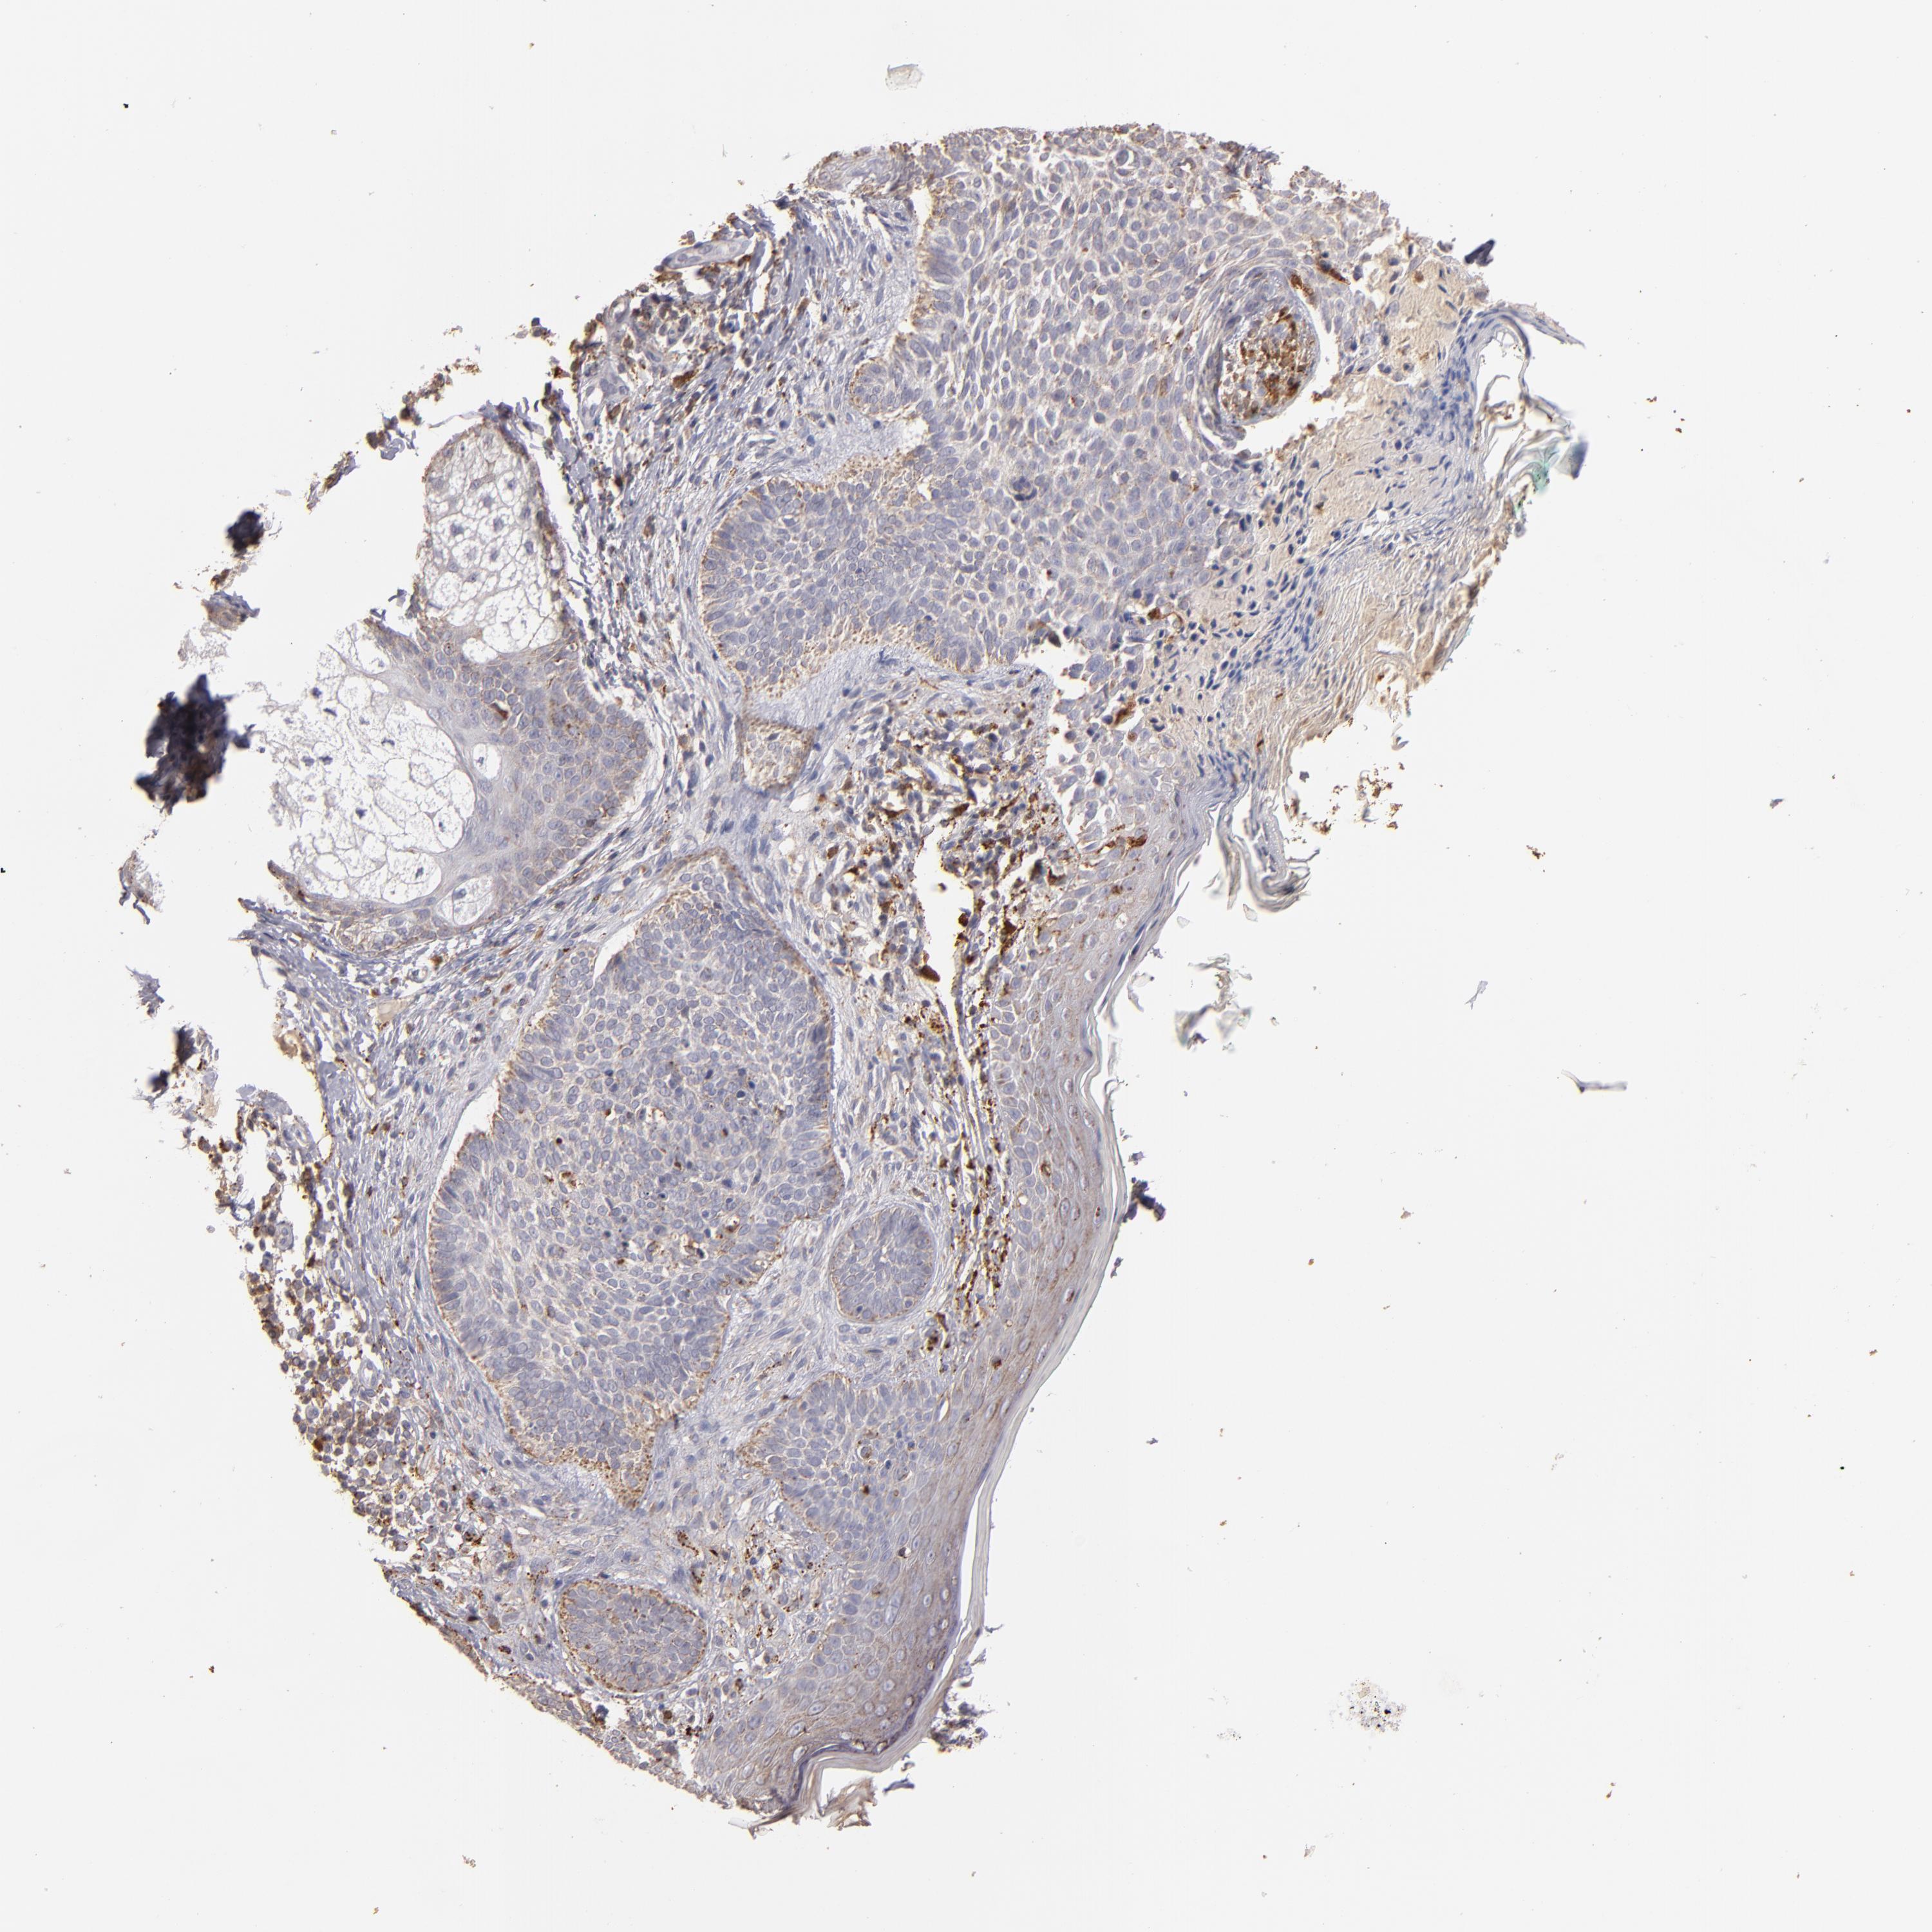

SKIN CANCER - Protein expressioni

A mouse-over function shows sample information and annotation data. Click on an image to view it in a full screen mode. Samples can be filtered based on level of antibody staining by selecting one or several of the following categories: high, medium, low and not detected. The assay and annotation is described here.

Each image is clickable and will lead to virtual microscopy that enables deeper exploration of all samples and also displays staining intensity scores, fraction scores and subcellular localization as well as patient and tissue information for each sample.

Antibody CAB009593

Squamous cell carcinoma, NOS

Basal cell carcinoma